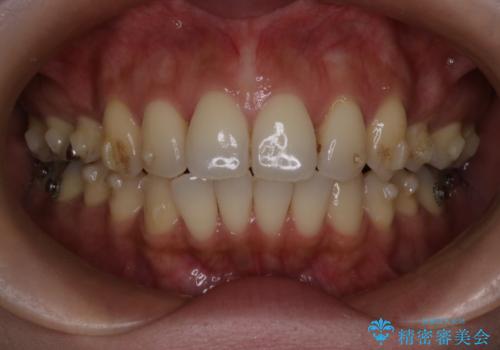

- 上の前歯の突出感を気にして来院された患者様です。

目立たない装置を希望とのことで、上顎左右第一小臼歯を抜歯し、インビザラインにて矯正治療を行うこととしました。